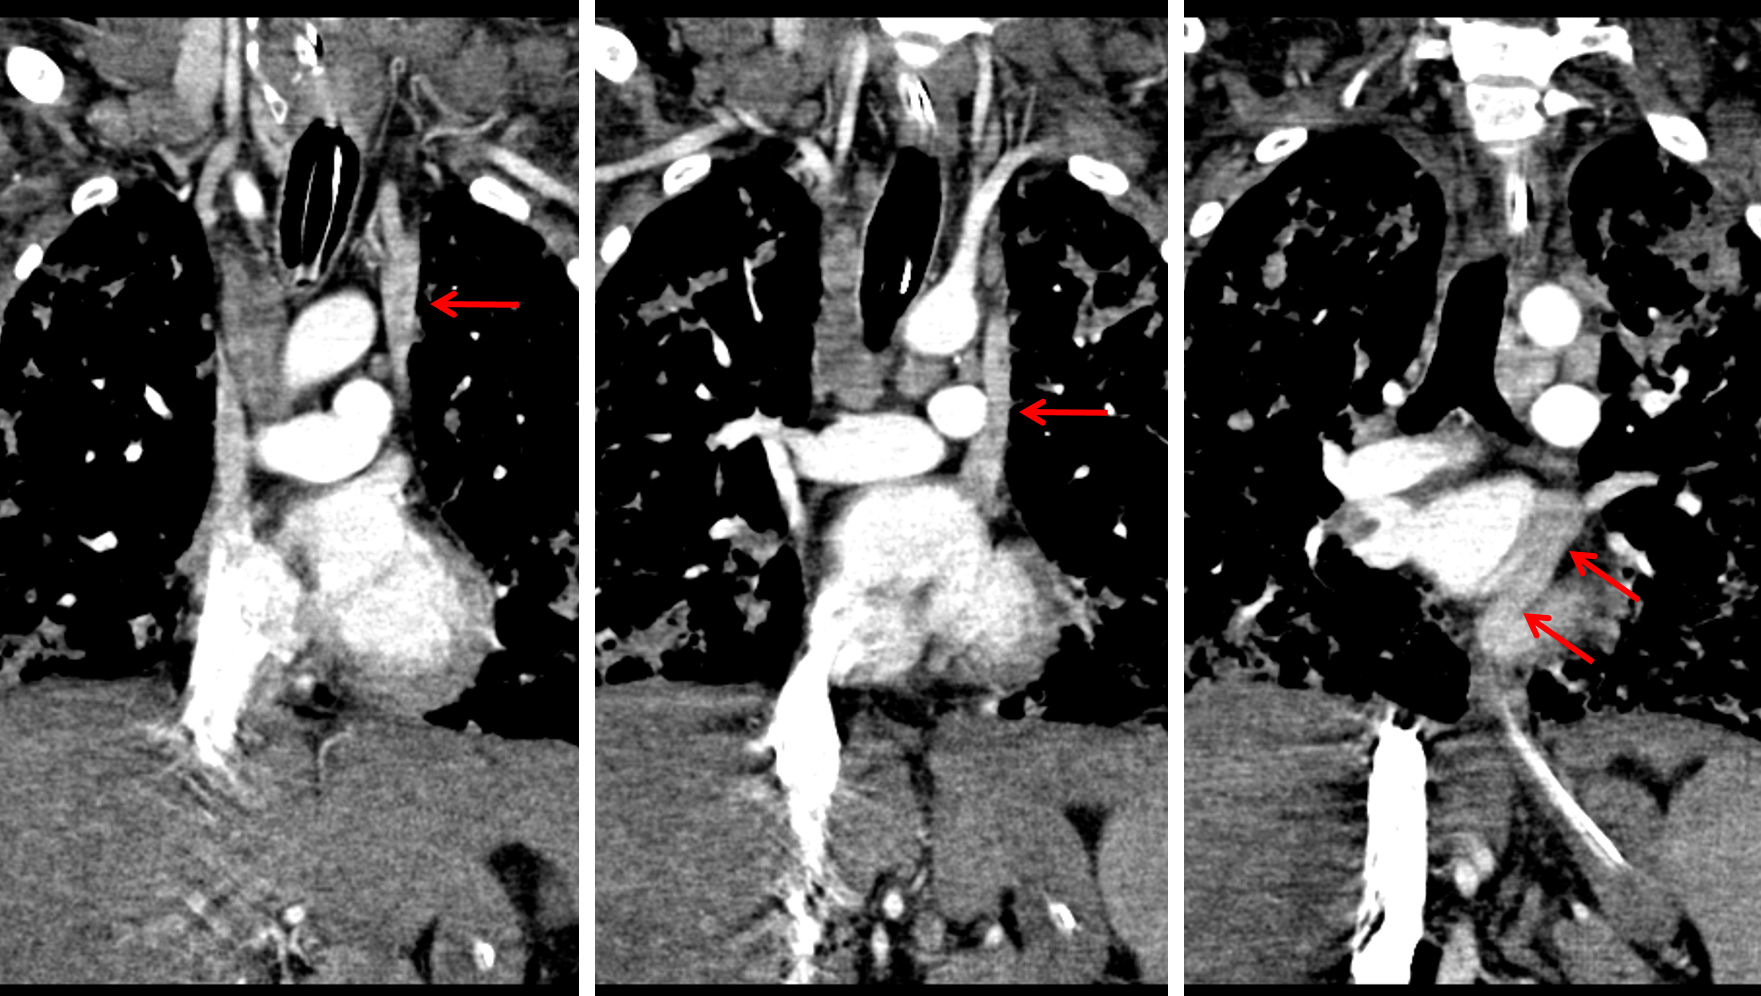

Sample ReportLeft upper extremity PICC courses inferiorly along the left aspect of the mediastinum, possibly within an anomalous venous structure such as a left SVC, though arterial placement is difficult to exclude on this single radiographic view. Recommend correlation with any available prior cross-sectional imaging and with blood gas sampling from the catheter.